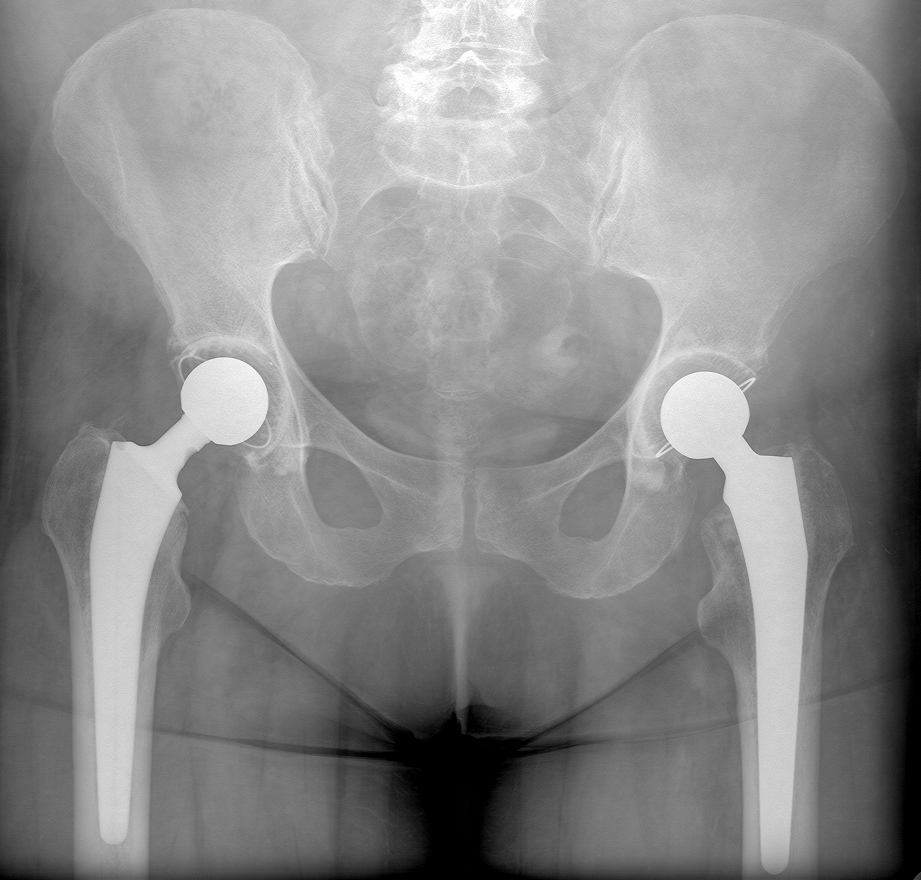

На следующей Rn-грамме правого тазобедренного сустава №3911 определяется состояние после металлоостеосинтеза пластиной и винтами после трансцервикального перелома проксимальной трети бедренной кости в 2021 г. Было проведено несколько операций, но сращение так до конца и получилось. Теперь такая картина: